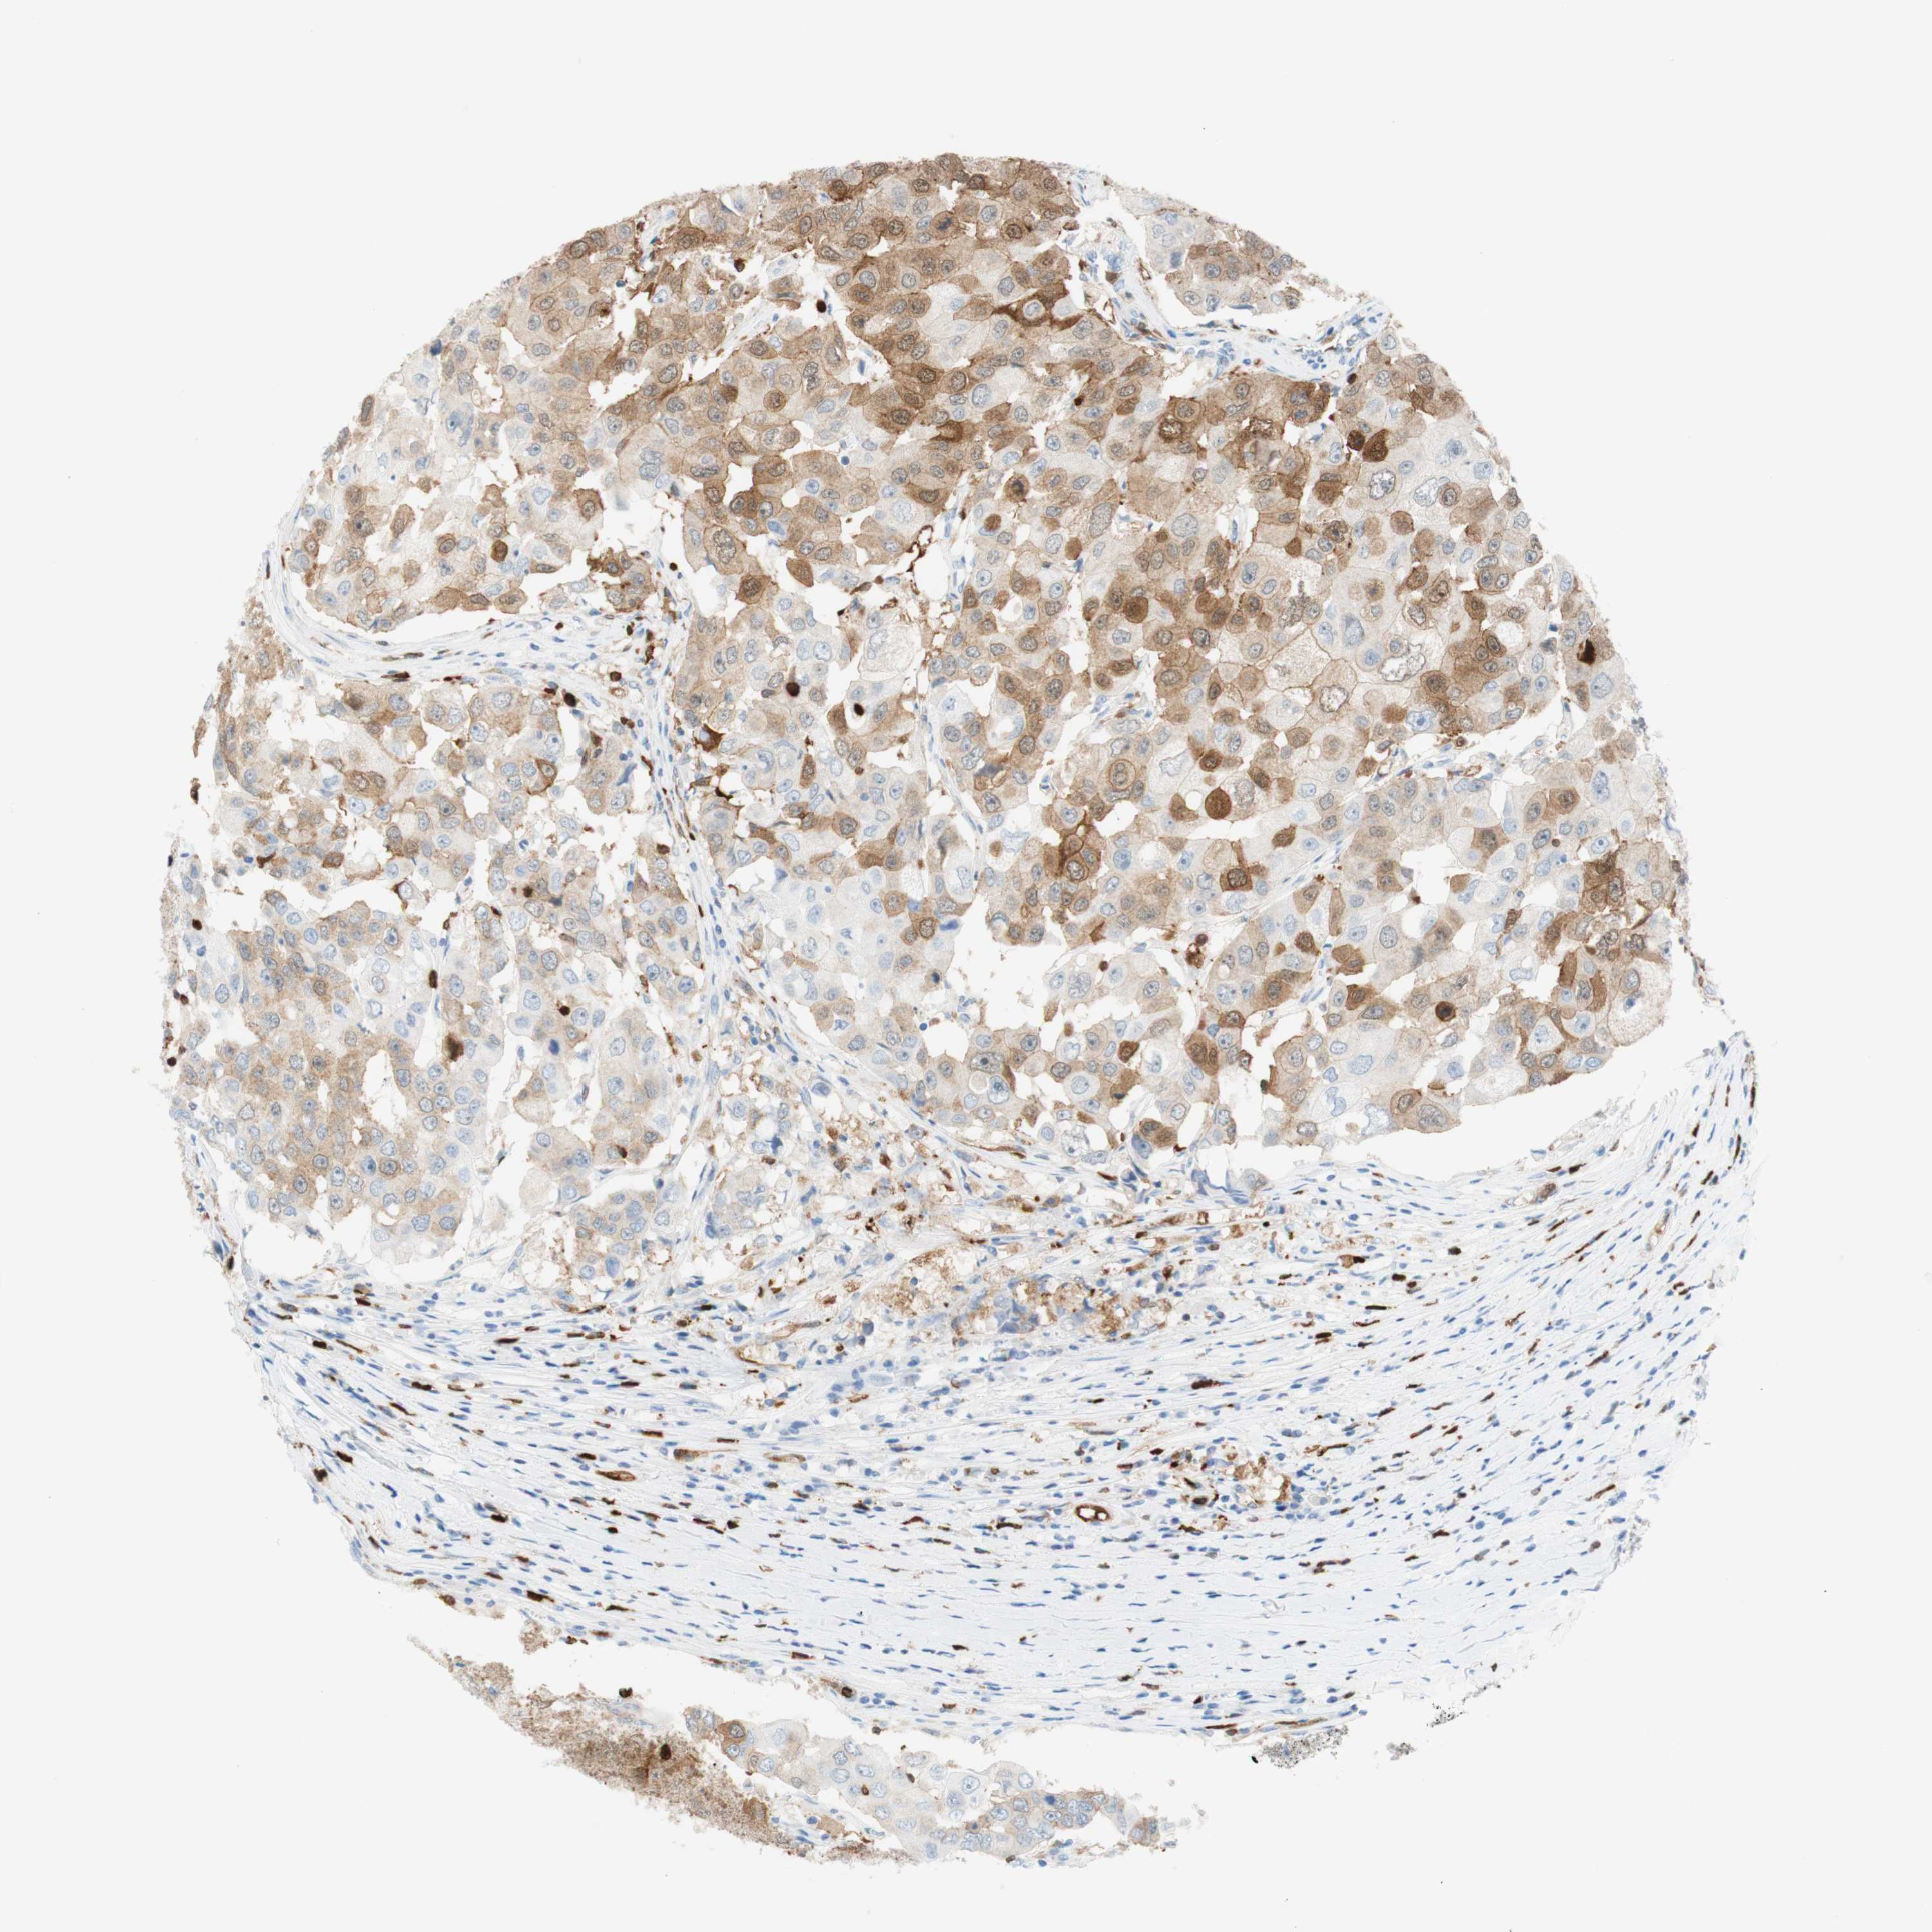

BRCA TCGA BRCA VALIDATION PROTEIN EXPRESSION

ANTIBODIES

AND

VALIDATION